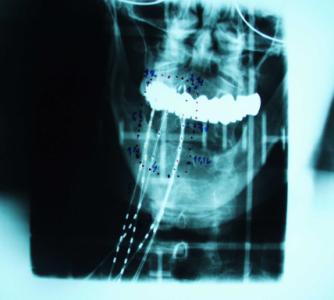

K plánování HDR brachyterapie se do nedávna využívaly snímky z C ramene, snímané v semiortogonální projekci (obr. č. 7 a 8), v posledních několika letech jsou využívány 3D snímky z CT (obr. č. 9).

Obrázek č. 7 Obrázek č. 8